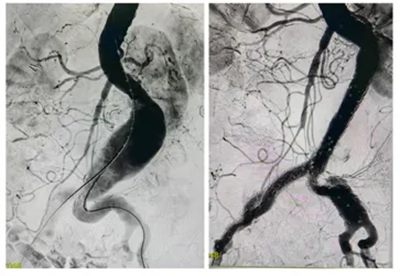

情况危急,血管外科团队迅速为刘奶奶安排了“腹主动脉覆膜支架腔内隔绝术”。

▲ 术中造影,腹主动脉局部瘤样扩张,行“覆膜支架隔绝”封堵良好

这是一种微创手术,仅用2小时就成功拆除了这颗“炸弹”。术后第3天,刘奶奶就能下地自如活动,腹痛也消失了,顺利康复出院。